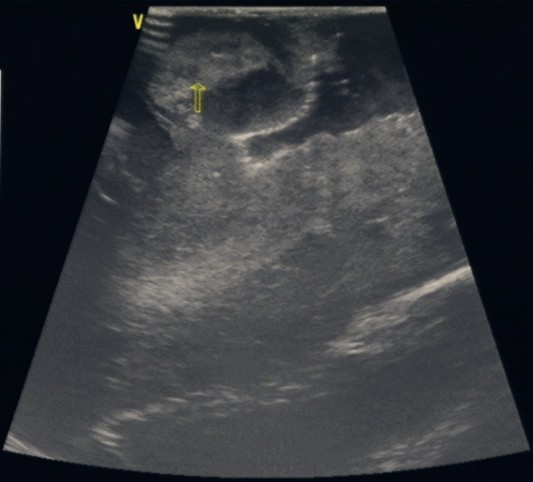

当天,在B超室的大力支持和配合下,手术顺利地进行。术中应用我院平常的床边B超机,选择一个与术区相当的B超探头,裹上无菌膜即可使用。在切除肿瘤过程中,用B超探头贴近术区探测肿瘤的范围及位置,在B超引导下一步步切除肿瘤。当手术行将结束时,再次应用B超探测,清楚地发现肿瘤残留,并进一步切除干净。结果,本例手术切除了95%以上的肿瘤组织,取得了圆满的成功。

1. 脑肿瘤术中B超应用

2.术中B超探测肿瘤

3.完全切除肿瘤